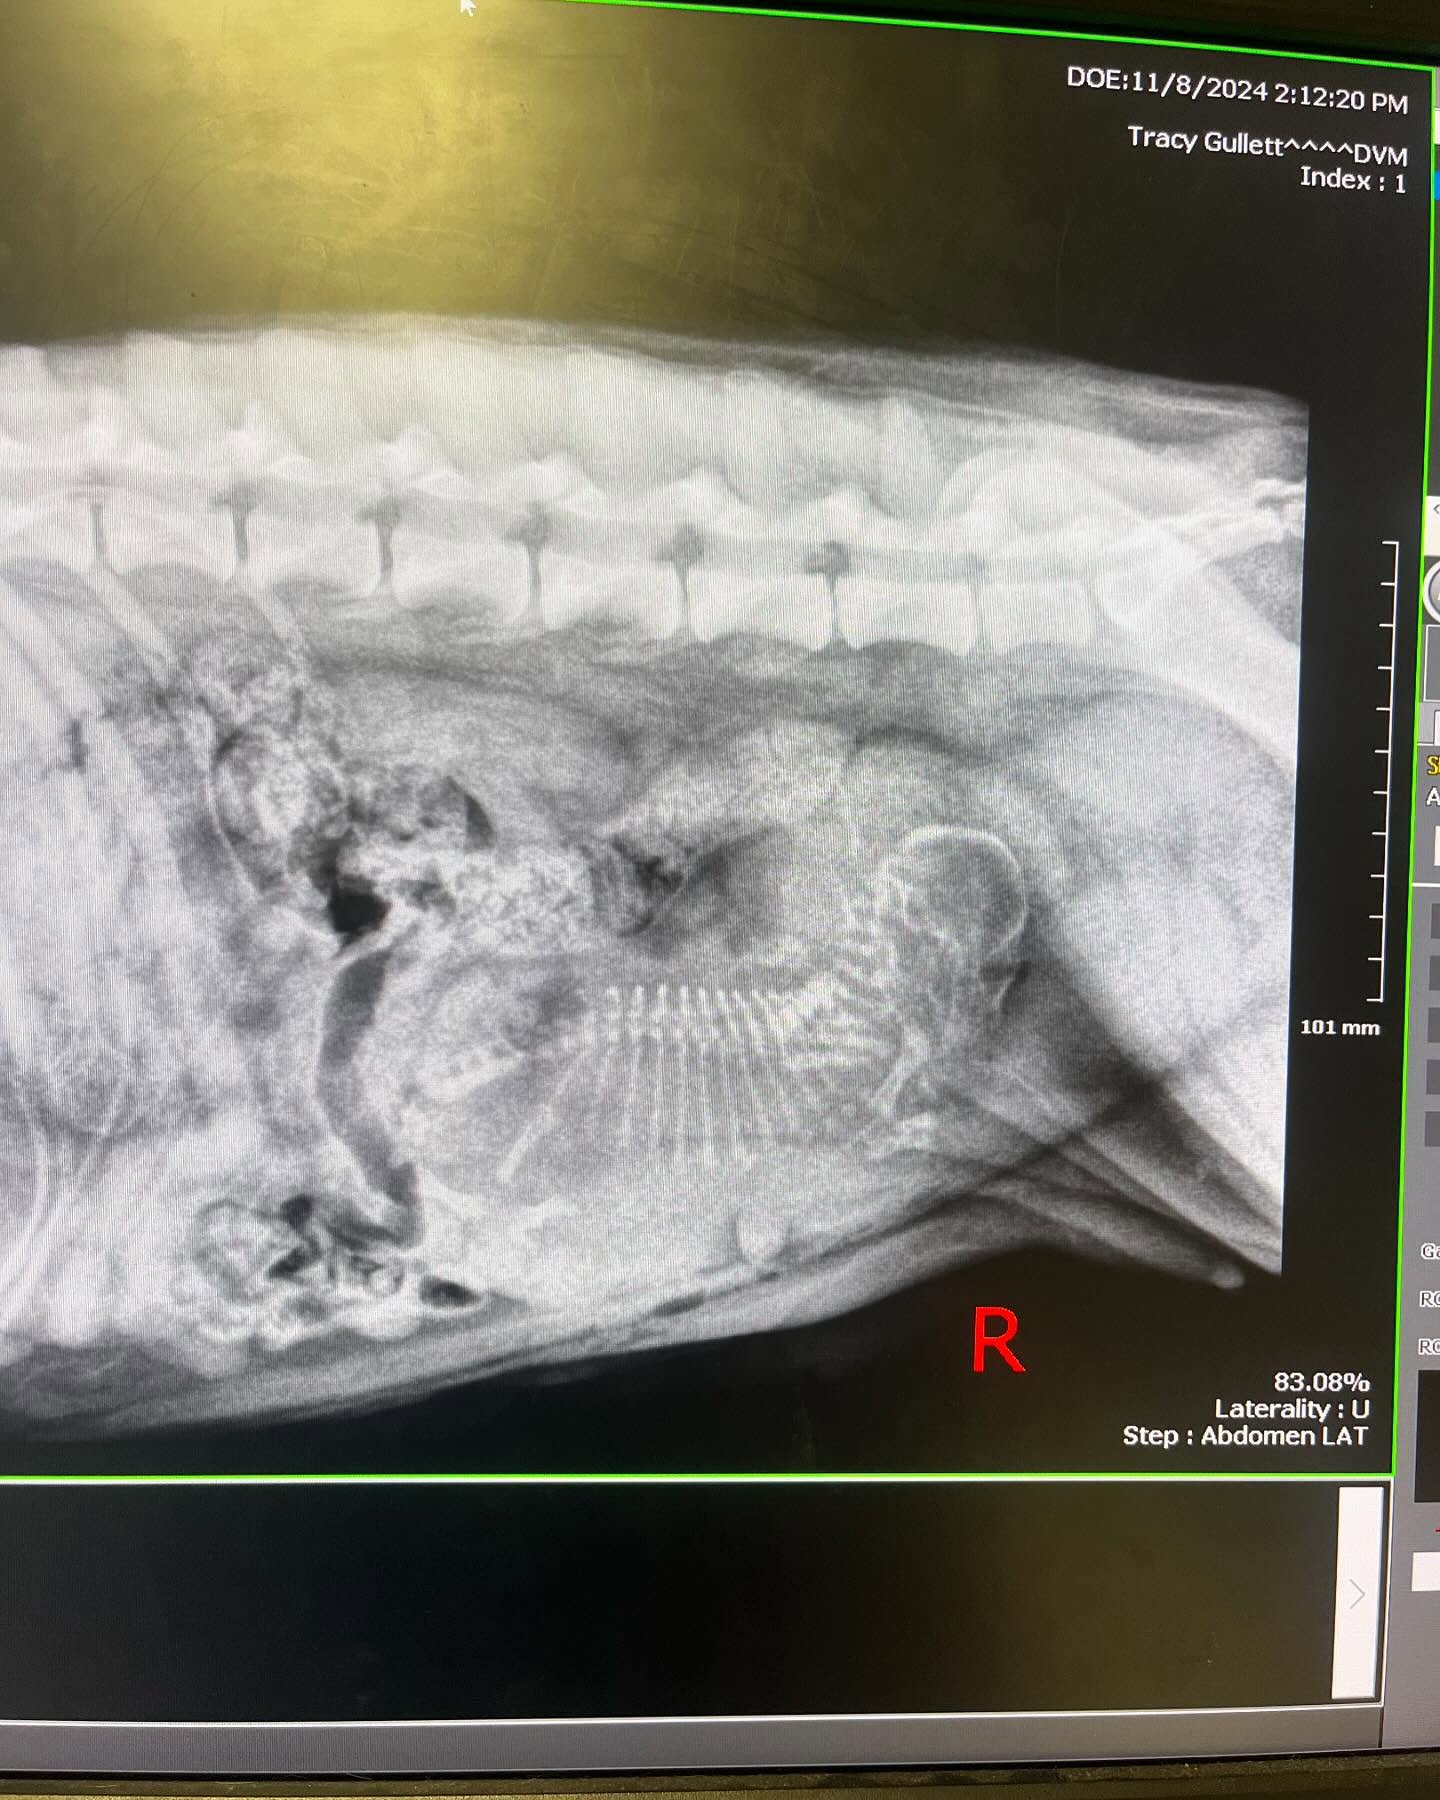

A few days later, the moment everyone had been waiting for finally approached. Before delivery, the veterinarian performed an X-ray to determine the size of the litter, and what they found left everyone stunned.

There was only one puppy. And she was enormous.

“We asked for an x ray to get a puppy count…Salem is pregnant with ONE puppy! One miracle puppy,” the rescue wrote.